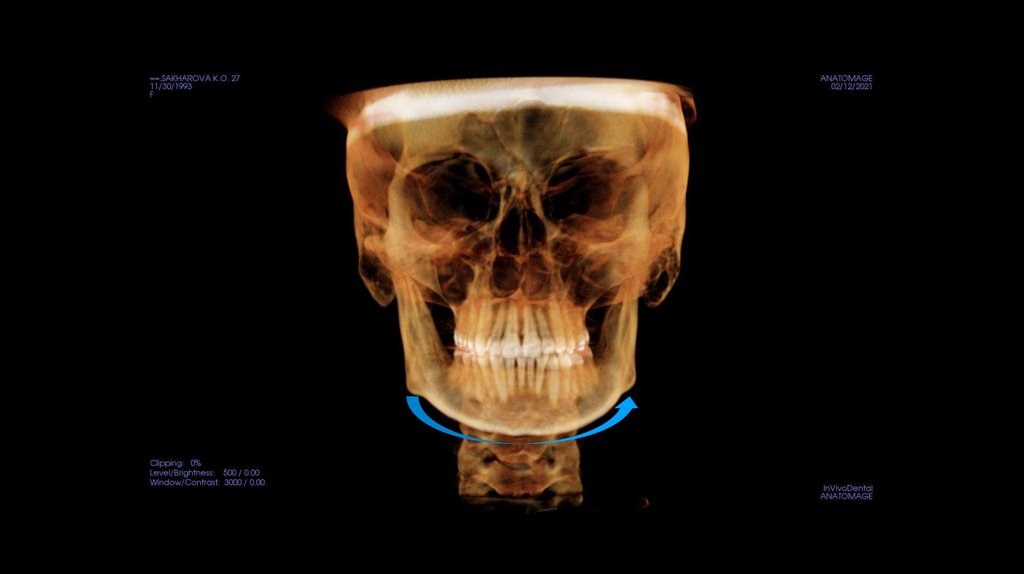

По рассчетам снимков:

• Ретрузия резцов верхней челюсти

• Компрессия головок суставов, особенно правого( началось

ремоделирование)

• Костная ассиметрия(10 мм)

• 2 класс

• 25, 46 зуб – нуждается в санации

• Требуется профессиональняа гигиена полости рта

• Клиновидные дефекты 43, 44

• 18, 28, 38, 48 отсутствуют.

Дентальный: II по молярам справа и слева, по клыкам

справа I, слева II, сужение верхнего зубного ряда,

обратная окклюзия (перекрест) в области 12 46 35,

трансверзальная резцовая окклюзия на 3-3.5 мм влево

взр, трансверзальная резцовая окклюзия на 1 мм вправо,

мезиализация 46, 47, 26, 27 . Тортоаномалия 12, 24, 25,

35.